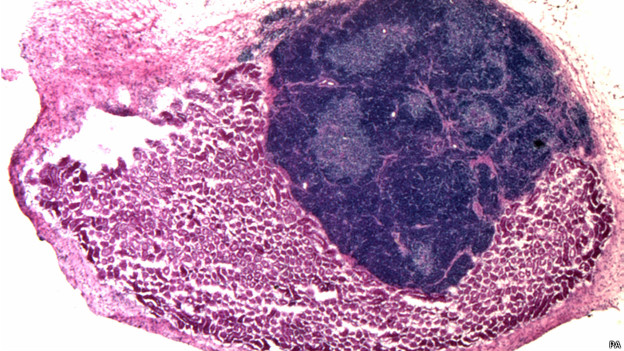

140825200513 orgao thymus pa 624x351 paUm timo – parte importante do sistema imunológico – de camundongo foi gerado artificialmente dentro de uma cobaia.

O timo é uma glândula linfática localizada próximo ao coração onde crescem importantes componentes do sistema imunológico, os chamados linfócitos T, que combatem infecções.

O timo é um órgão relativamente simples e, nos experimentos conduzidos pelos cientistas, manteve todas as suas funcionalidades normais. Estruturalmente, o órgão continha duas grandes regiões – o córtex e medula – e também produzia linfócitos T.